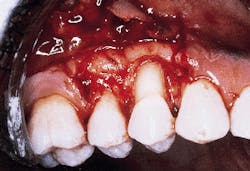

The defect subsequent to flap elevation can be seen in photograph #2. Calculus is evident on the buccal root surface.

Photograph #2: Subsequent to flap elevation a large piece of calculus is observed on the facial aspect of tooth #5.